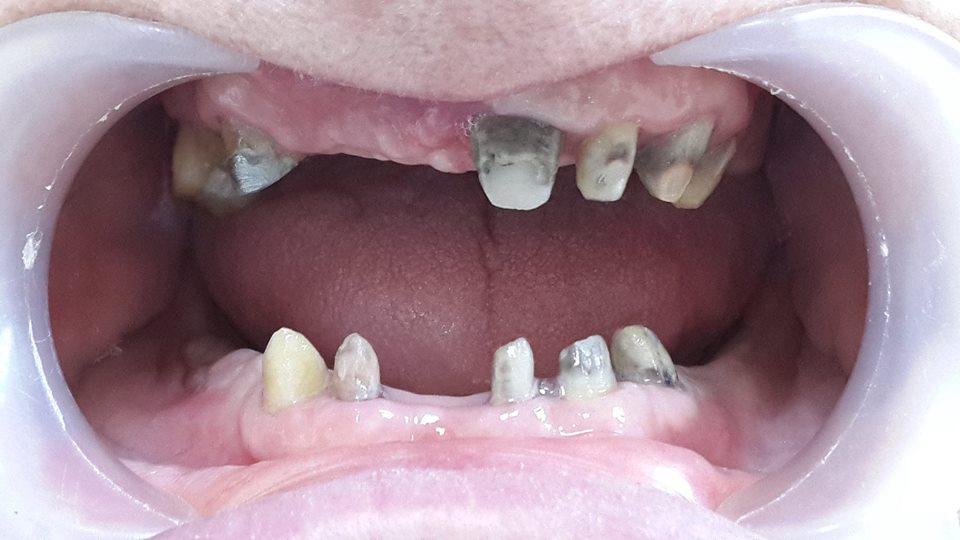

An example of complete rehabilitation of the oral cavity. Treatment included the removal of the old prosthesis, treatment of paradontitis, removal of a large cyst, implantation, clasp prosthesis.